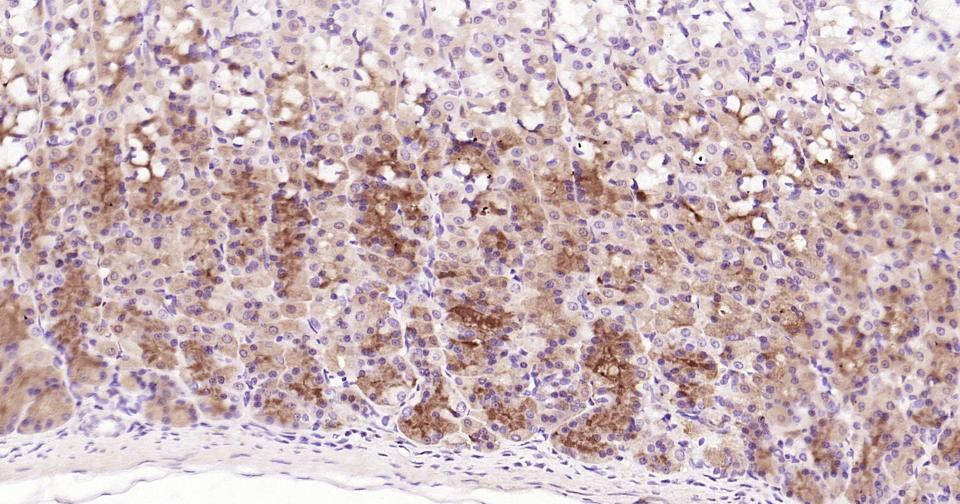

Paraformaldehyde-fixed, paraffin embedded Mouse Pancreas; Antigen retrieval by boiling in sodium citrate buffer (pH6.0) for 15 min; Antibody incubation with Notch1 Monoclonal Antibody, Unconjugated(bsm-60871R) at 1:200 overnight at 4°C, followed by conjugation to the bs-0295G-HRP and DAB (C-0010) staining.